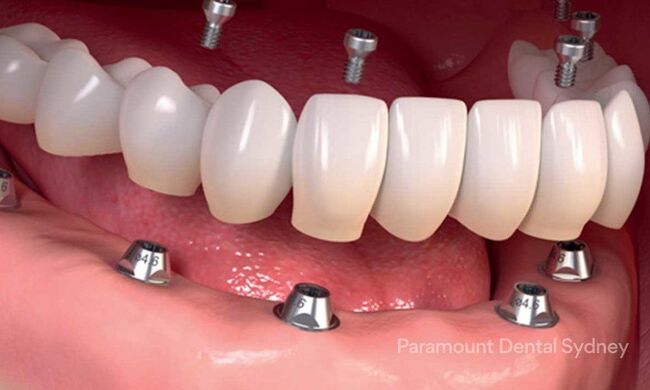

ایمپلنت دندان یک روش درمانی مناسب برای جایگزین کردن دندان های از دست رفته می باشد. ایمپلنت دندان ها از مزایای زیادی برخوردار است اما متاسفانه در کنار این مزایا، عوارضی نیز مشاهده می شود. در این مقاله سعی شده است تا به تمامی عوارض ایمپلنت دندان اشاره کرده و آن ها را مورد بررسی قرار دهیم. عوارض ایمپلنت دندان ممکن است در دراز مدت و در کوتاه مدت با یکدیگر تفاوت هایی داشته باشند.

موارد زیر از جمله عوارض ایمپلنت دندان می باشند: